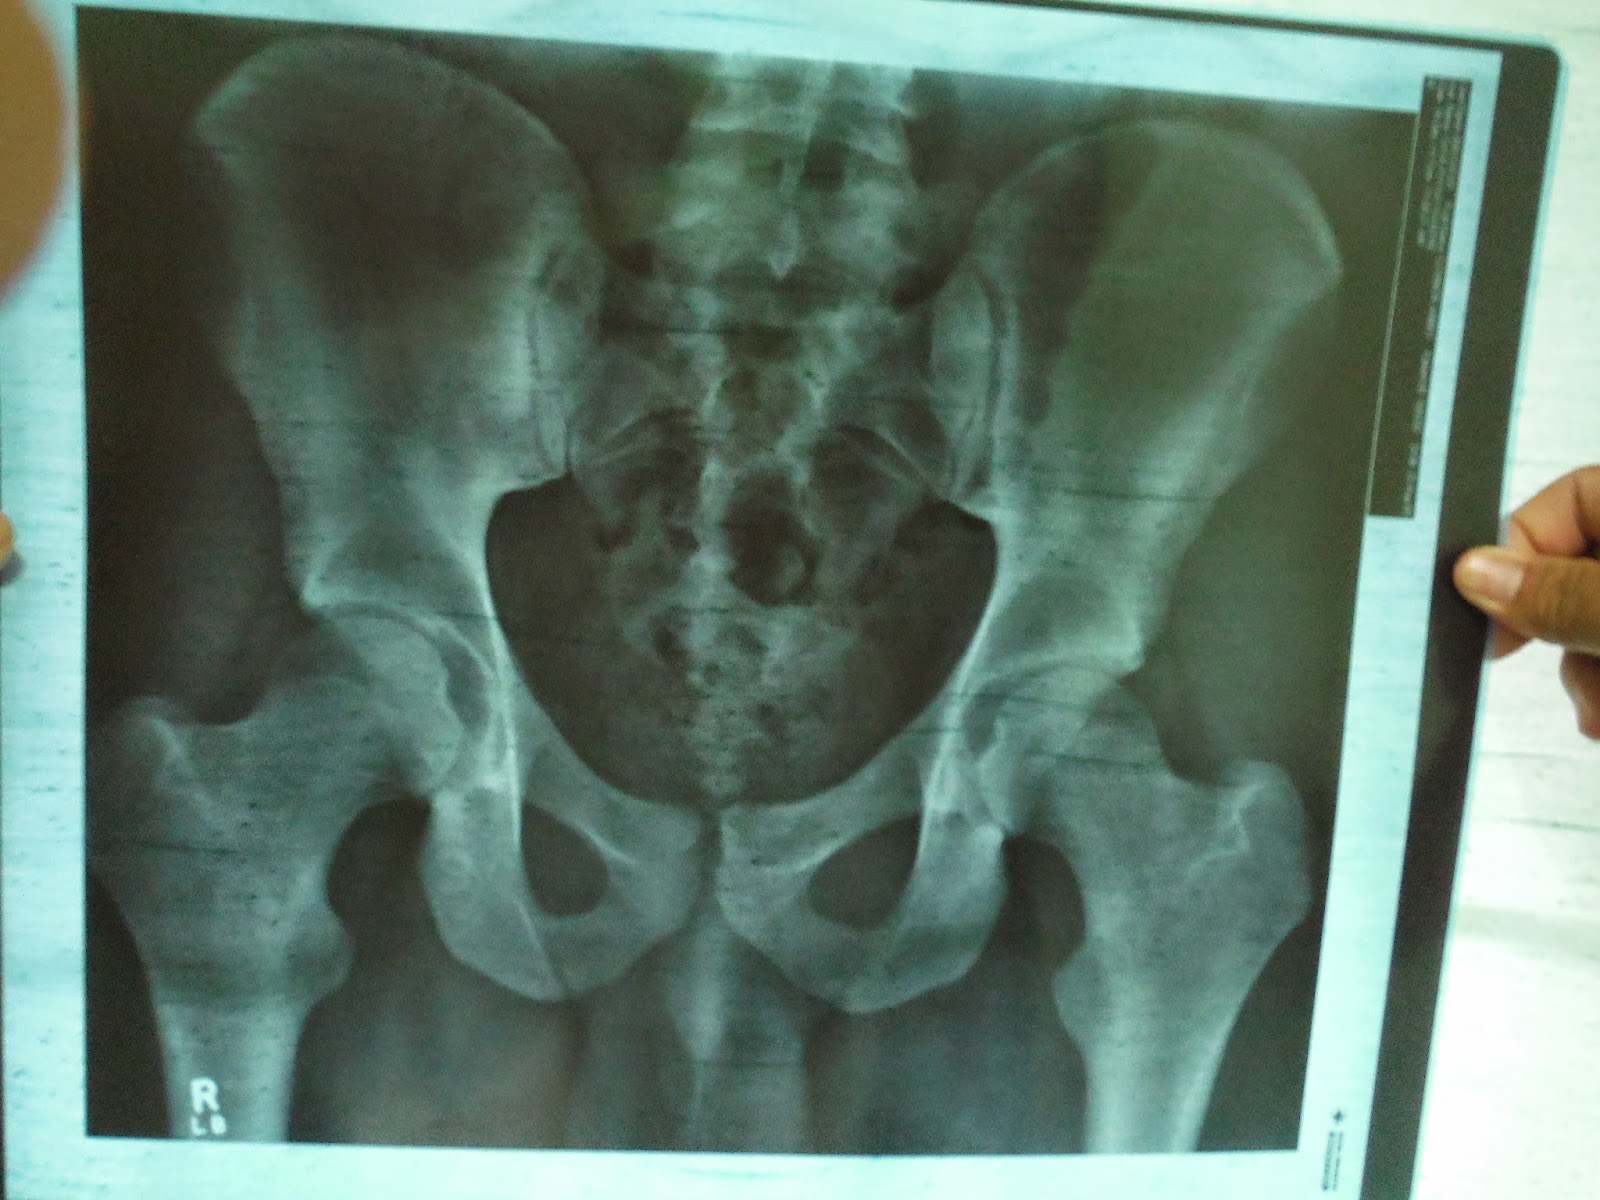

Well, we got back and had church and stuff same ole, same ole. Then went to a fireside, and came back. Well, here are my results. My hip has been pulled out of place by tight muscles. Show choir helped me with something, so I need a thank you to go to Sister Gull and Mr. Child. The Physical therapist said I was the most flexible guy he had worked with, which at first I didn't think I was flexible, but I was able to lay my knees flat to my chest. I almost got my legs straight, but they stopped still a bit bent. Well, I quickly grabbed the x-ray picture, and took a picture of it for you peeps! It is a good pelvis, just one hip is pulled slightly making it shallow. This means I makes my hip pull into a natural relax as I walk, which is causing the pain, cause my hip is pushing out wrong. (They gave him some exercises to do and taught him how to do real, effective lunges to stretch.)

My hip x ray